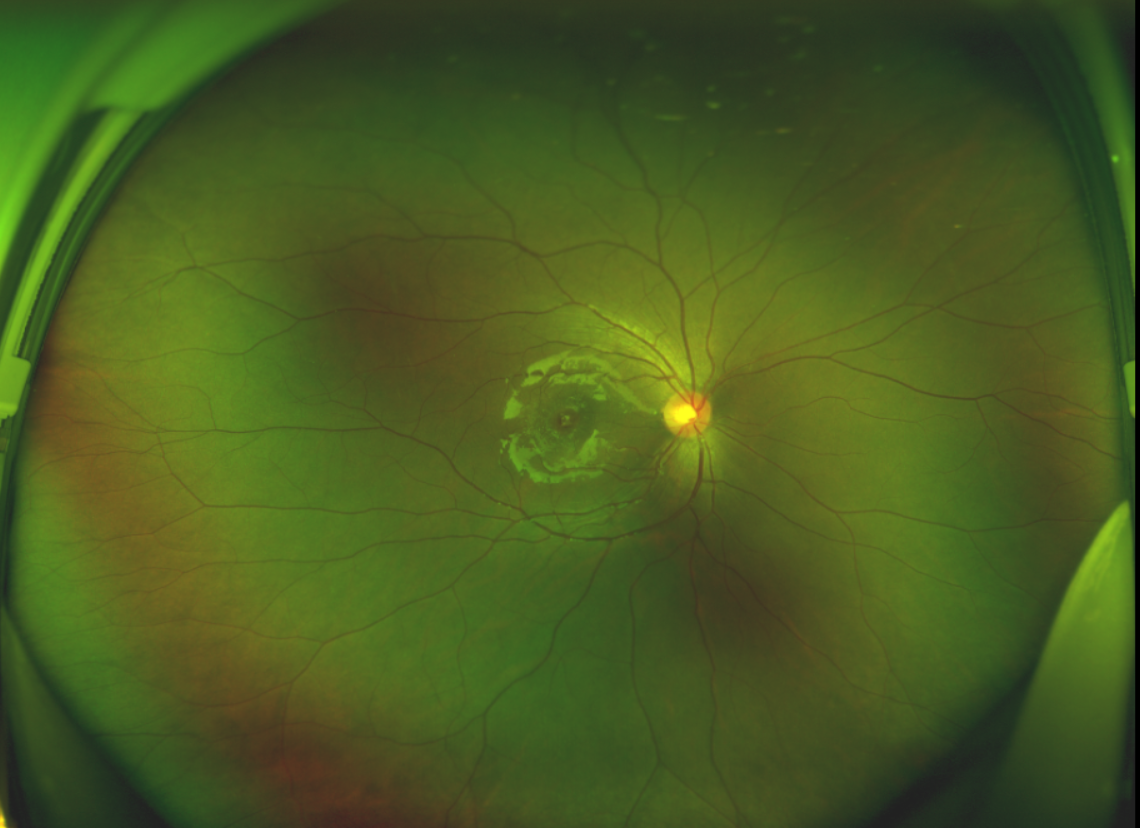

黃斑位于視網(wǎng)膜正中心,是視覺最敏銳的區(qū)域,堪稱“眼底的心臟”,負(fù)責(zé)我們閱讀、駕駛、識(shí)別人臉等精細(xì)視覺。 當(dāng)黃斑區(qū)的神經(jīng)組織出現(xiàn)全層缺損,形成一個(gè)“孔洞”,即為黃斑裂孔,它會(huì)直接導(dǎo)致中心視力急劇下降、視物變形、視野中心出現(xiàn)暗區(qū)。

經(jīng)過詳細(xì)的檢查和評(píng)估,王曉波主任決定采用“內(nèi)界膜翻轉(zhuǎn)覆蓋聯(lián)合粘彈劑固定術(shù)”為誠誠進(jìn)行治療。

術(shù)中,醫(yī)生精細(xì)剝離黃斑區(qū)的內(nèi)界膜后,并非直接丟棄,而是巧妙地給它翻個(gè)面,讓它變成一塊天然“創(chuàng)可貼”,嚴(yán)密覆蓋在黃斑裂孔的表面。覆蓋的內(nèi)界膜像微型支架一樣撐住裂孔邊緣,防止它擴(kuò)大;同時(shí),這層膜本身含有能促進(jìn)生長的“養(yǎng)分”,能顯著刺激裂孔周圍的視網(wǎng)膜組織像爬山虎一樣快速生長、蔓延過來,最終把裂孔“補(bǔ)”好。

除此之外,利用自體組織覆蓋為黃斑裂孔提供了理想的愈合環(huán)境,裂孔閉合速度顯著快于傳統(tǒng)方法。誠誠接受手術(shù)24小時(shí)后,檢查可見內(nèi)界膜瓣位置良好;術(shù)后1個(gè)月,黃斑裂孔已經(jīng)閉合,視力恢復(fù)到0.5;術(shù)后兩個(gè)月,視力進(jìn)一步提升到0.7。